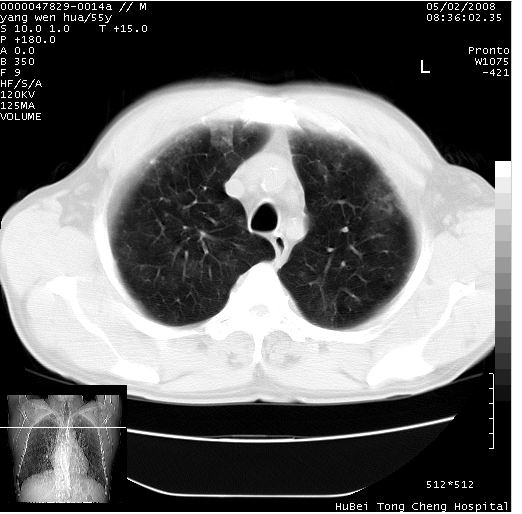

以下是引用lisihao在2008-5-3 23:25:00的发言:[br]双肺多发小片云雾状阴影,结合病史,多考虑支气管扩张并咯血进入肺泡所致

以下是引用tao772在2008-5-4 16:03:00的发言:[br]影像学表现:双肺弥漫性毛玻璃样、棉絮样阴影,密度不均,边缘模糊,两次片比无明显变化,纵隔内未见明确异常密度影,双侧胸腔内见少量水养密度影。[br] 拟诊:(1)肺出血性疾病(肺肾综合症?)[br] (2)感染性疾病(考虑机遇性感染)[br] (3)过敏性肺炎、肺泡蛋白沉积症。[br] 建议完善实验室检查、完善病史。[br] 相关的鉴别诊断:[br] 1.肺水肿:1)肺水肿的阴影密度较均匀,有时如毛玻璃样。2).肺水肿有间质异常阴影,如肺纹理的模糊、增粗,有间隔线阴影。3)肺水肿阴影的动态变化大,几小时、数天内有显著的增多或减少。4)肺水肿不具备炎性的临床表现。[br] 2.ards:从现有的病史及临床表现可排除(约在发病7天后肺部的影像学表现可逐渐消失。)[br]